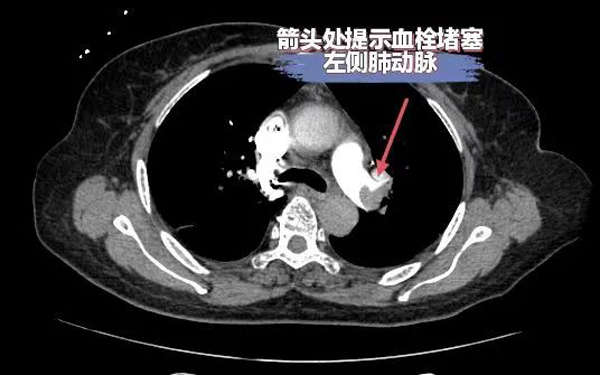

据了解,邓某,因“反复呼吸困难10余天”于外院治疗,效果不佳,症状逐渐加重,辗转多家医院来到我院,入院后患者生命体征不稳定,血压在70/40mmHg左右,心率120次/分左右,面罩吸氧状态下氧饱和度82%,D二聚体明显升高,高度怀疑肺栓塞,行急诊肺动脉CTA检查提示:右肺动脉主干及右肺下叶肺动脉分支血栓形成及下腔静脉大量血栓。